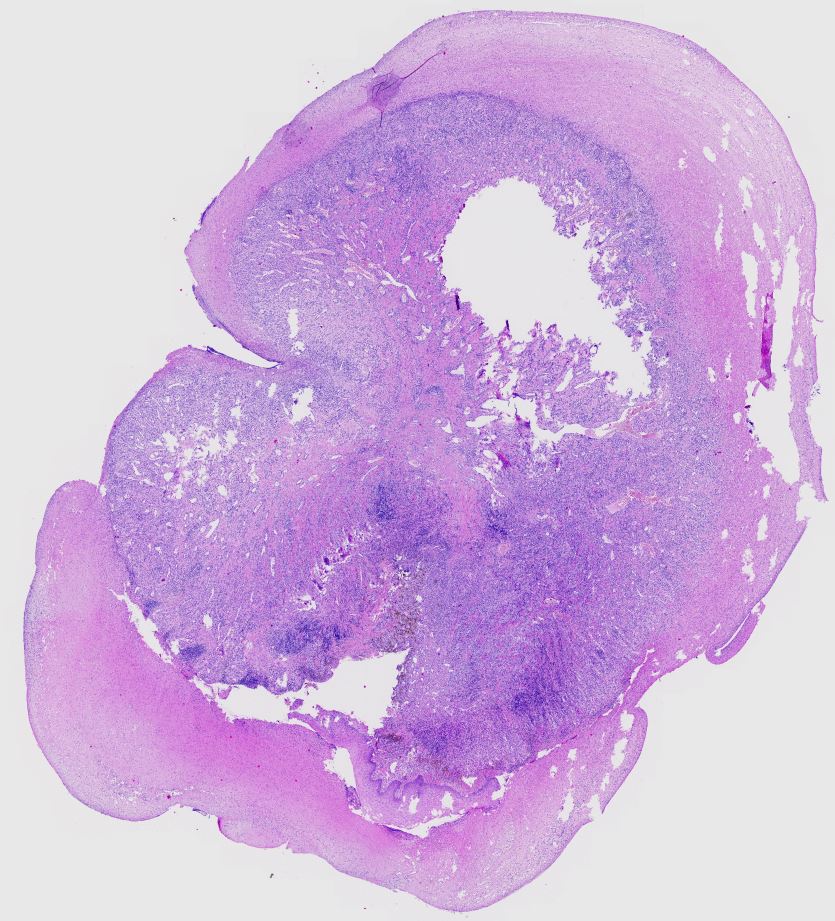

Piyano tuşlu böbrek tümörü Clear cell papillary renal cell tumor. Nuclei are piano key appearance **Note:** Tiles are generated locally and included in the repository. Manually commit and push to GitHub to make the viewer work.